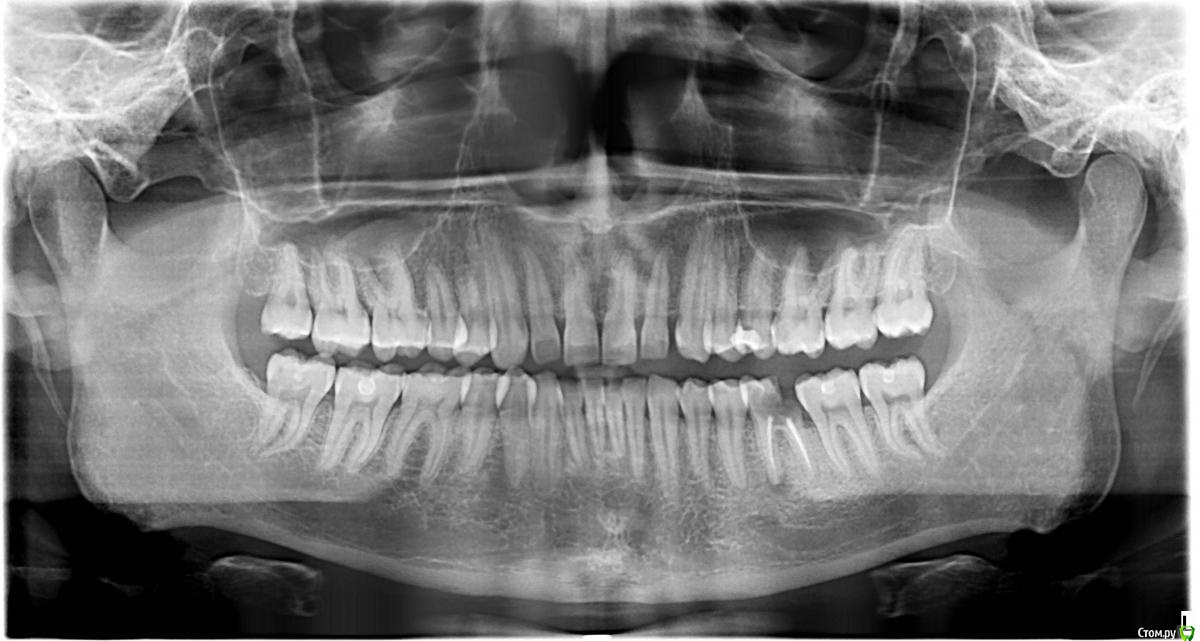

slk5001 Опубликовано 18 июля, 2018 Поделиться Опубликовано 18 июля, 2018 Здравствуйте! Что делать с 36 зубом?Какие варианты есть? Ссылка на комментарий

St. Опубликовано 19 июля, 2018 Поделиться Опубликовано 19 июля, 2018 Можно оставить как есть? нет, может разболеться и еще соседние зубы испортить за счет застревания пищи между ними Или поставить пломбу? нет, для постановки пломбы зуб слишком разрушенюАльтернативный вариант ( если при очном осмотре от зуба осталось достаточно )- перелечить каналы и накрыть зуб коронкой Ссылка на комментарий

red_butler Опубликовано 20 июля, 2018 Поделиться Опубликовано 20 июля, 2018 А почему удалять? Можно оставить как есть? Или поставить пломбу?Слишком поздно, объём оставшихся твёрдых тканей не позволяет восстановить зуб Ссылка на комментарий